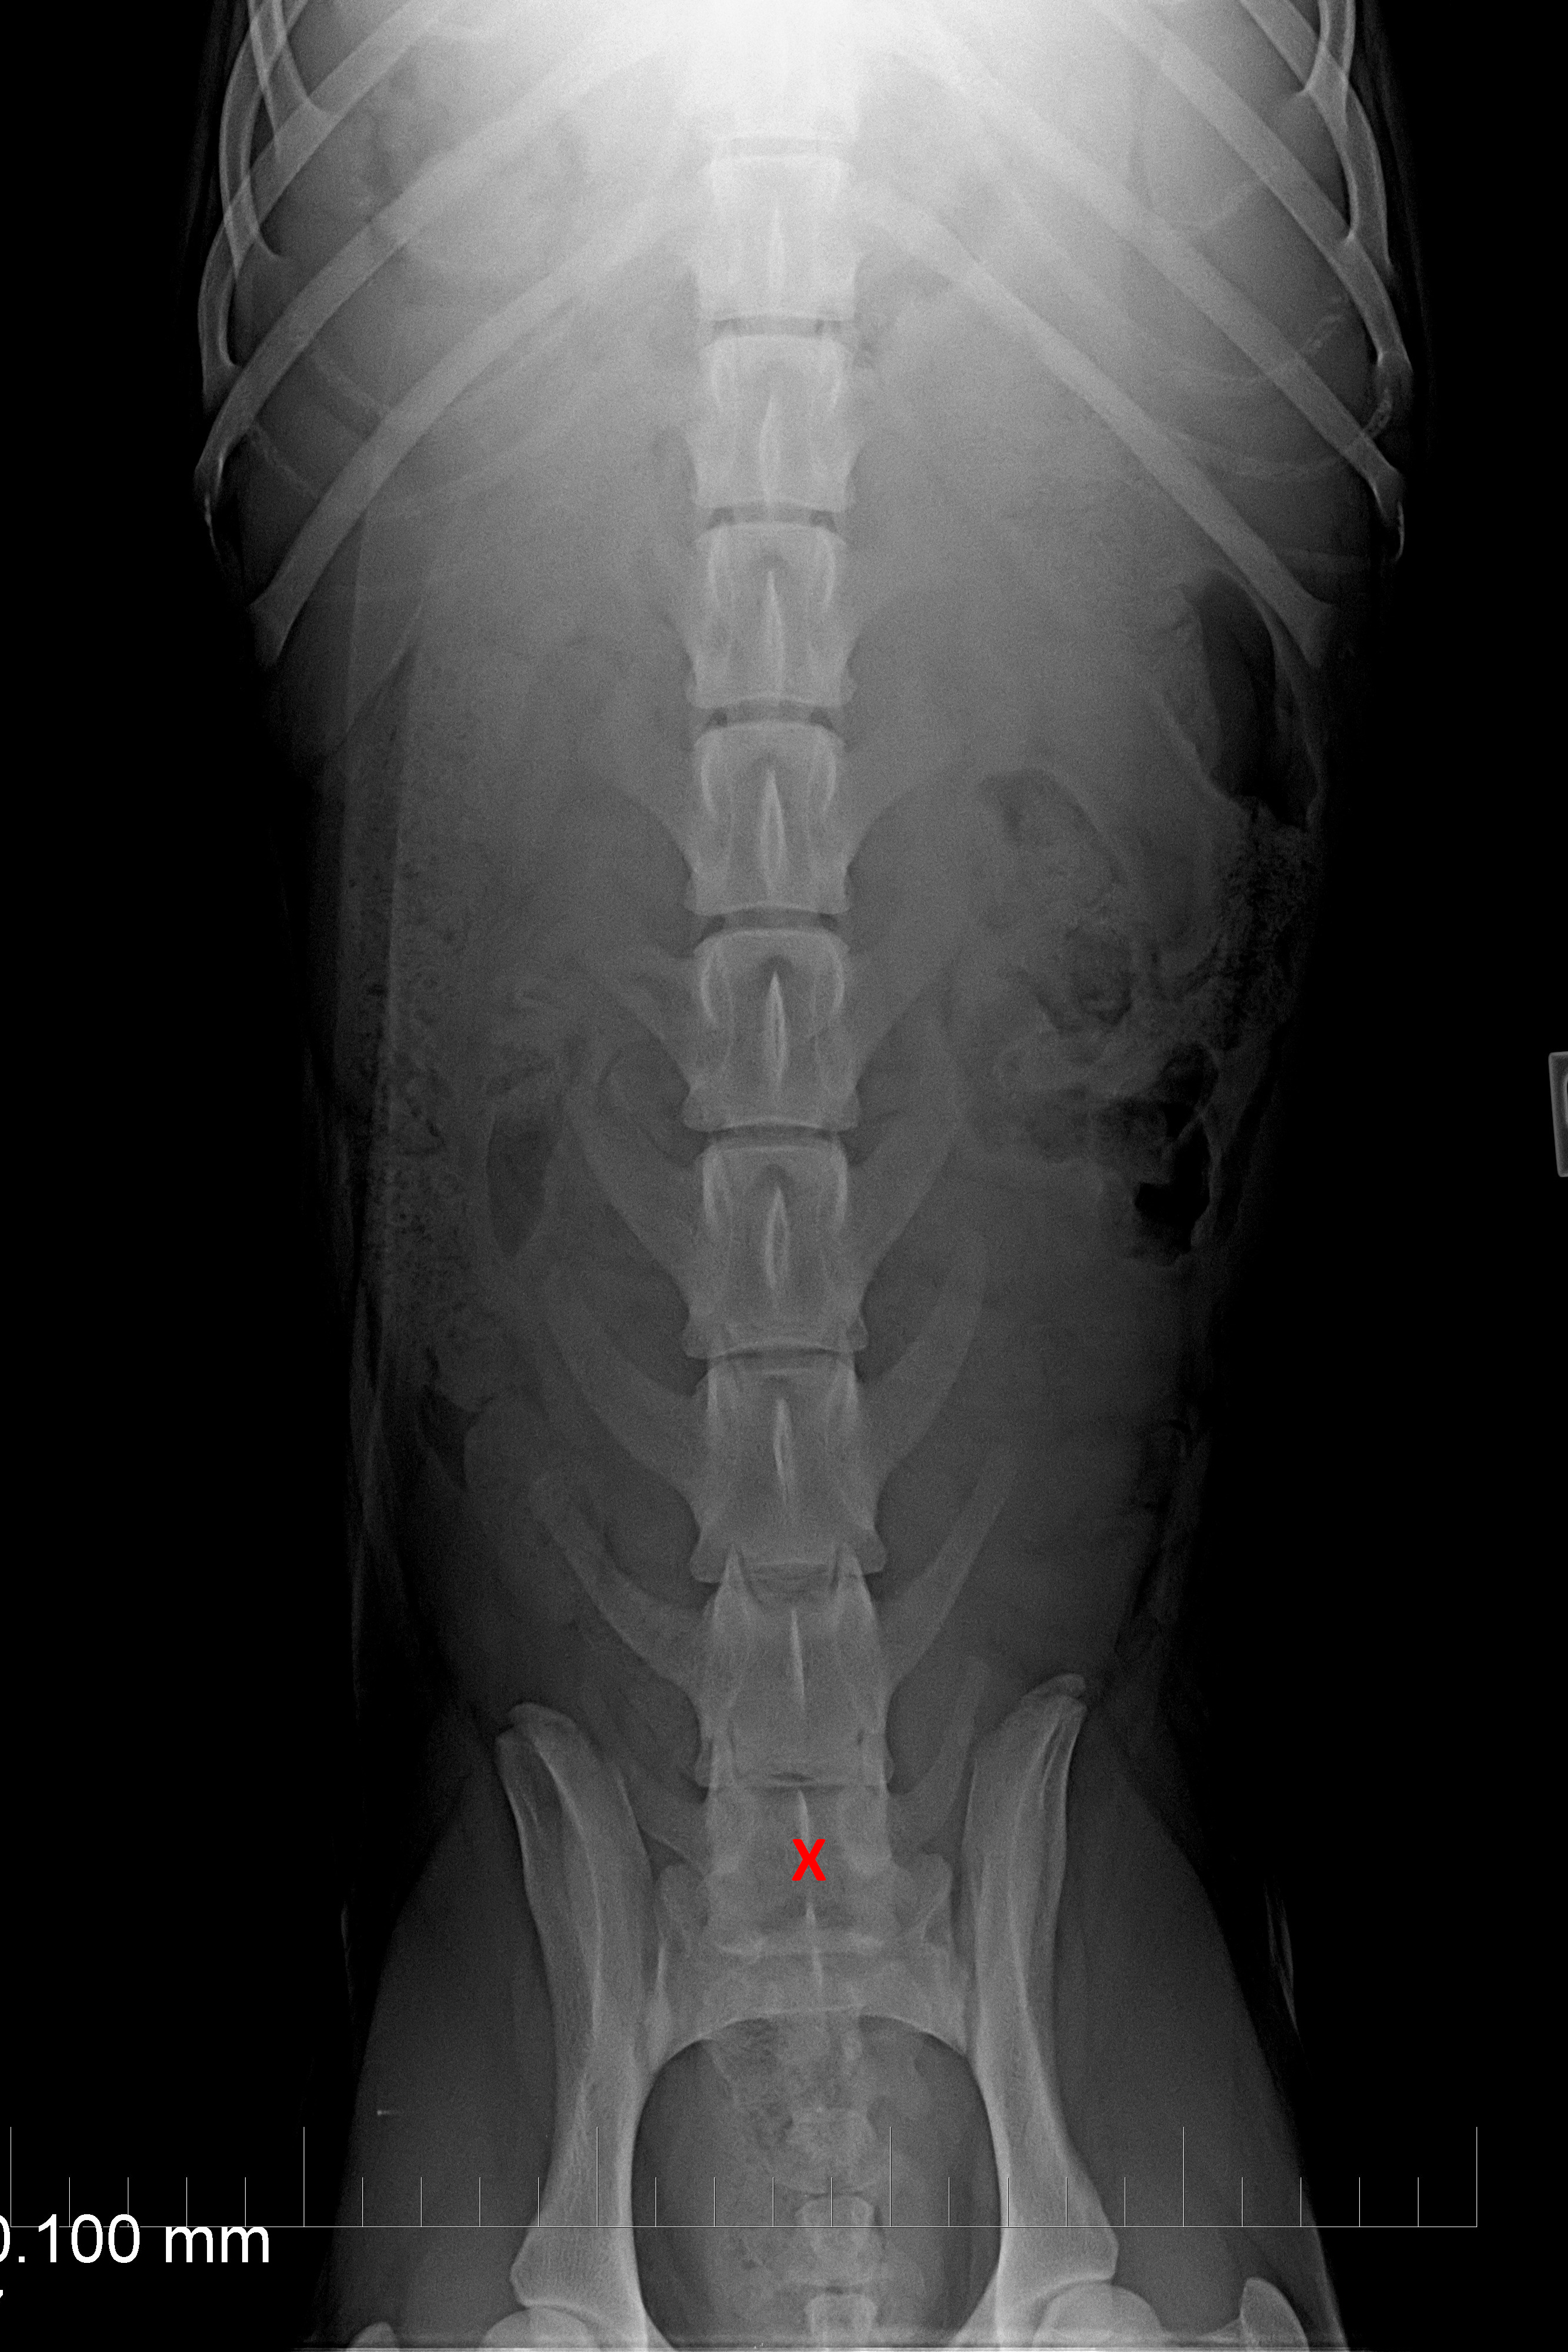

páteř VD

typ 3 u sedmiletého křížence